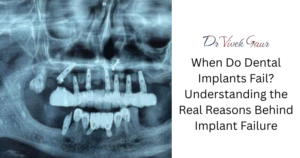

Dental implants have transformed modern dentistry by providing patients with a permanent and functional replacement for missing teeth. However, not all